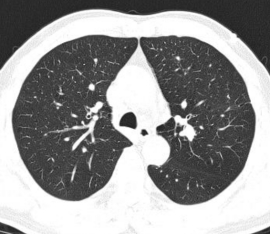

图2 术前胸部 CT 纵隔窗,清晰显示病灶解剖位置,位于中央气道以远的外周肺组织

患者因体检发现左肺结节就诊,胸部CT提示左肺固有上叶尖后段存在微小病灶,病灶位于肺野外周,远离中央气道,普通支气管镜无法直视及抵达病灶,常规活检手段阳性率极低,难以明确病理性质。